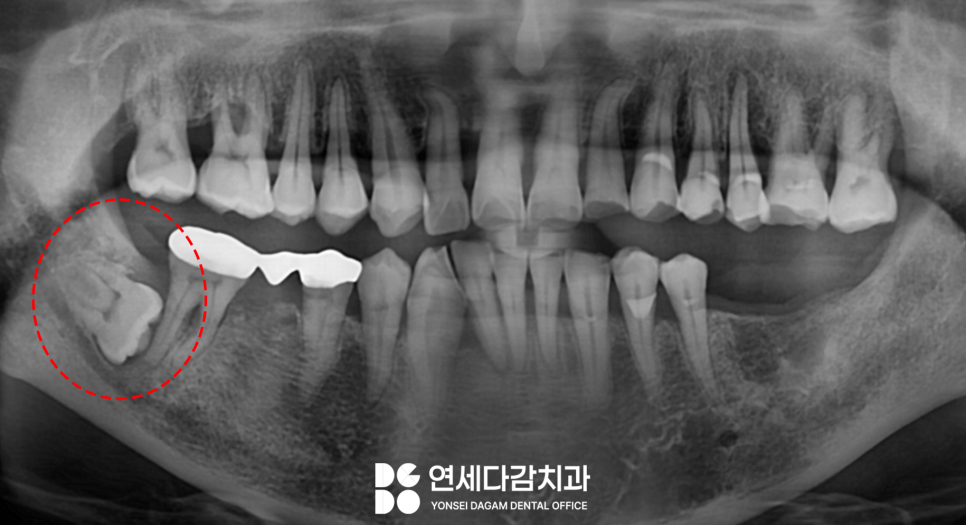

오금역 치과 에서

파노라마 사진에

표시한 부위를 보면

수평으로 매복되어 있는

형태였는데요.

이를 빼기 전 정확한 진단을 위해서

CT를 촬영하여 주위 구조를

3차원적으로 분석합니다.